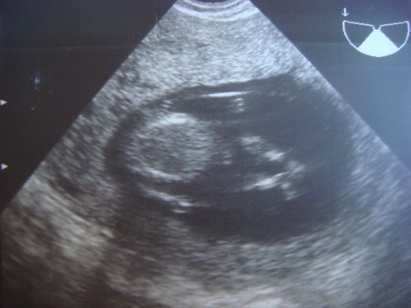

Pocimaci CRL 59,4mm hosszú, BPD 21mm, combcsont 9mm :lol: és a lényeg: NT 1,1mm.

Szóval minden a legnagyobb rendben. Méretei szerint akár egy héttel idősebb is lehet. Luca 12+6naposan volt CRL 60mm.

Megint riszált, szóval ajánlom, hogy lány legyen! :lol:

Jól átbogarásztuk a gerincét, kezeit, lábait. Tetőtől talpig megkukkoltuk!

Na a képek (a második babafotól látjátok, hogy összeüti az apró lábait. Kb fél cm lehet, vagy annyi sem egy tappancs):